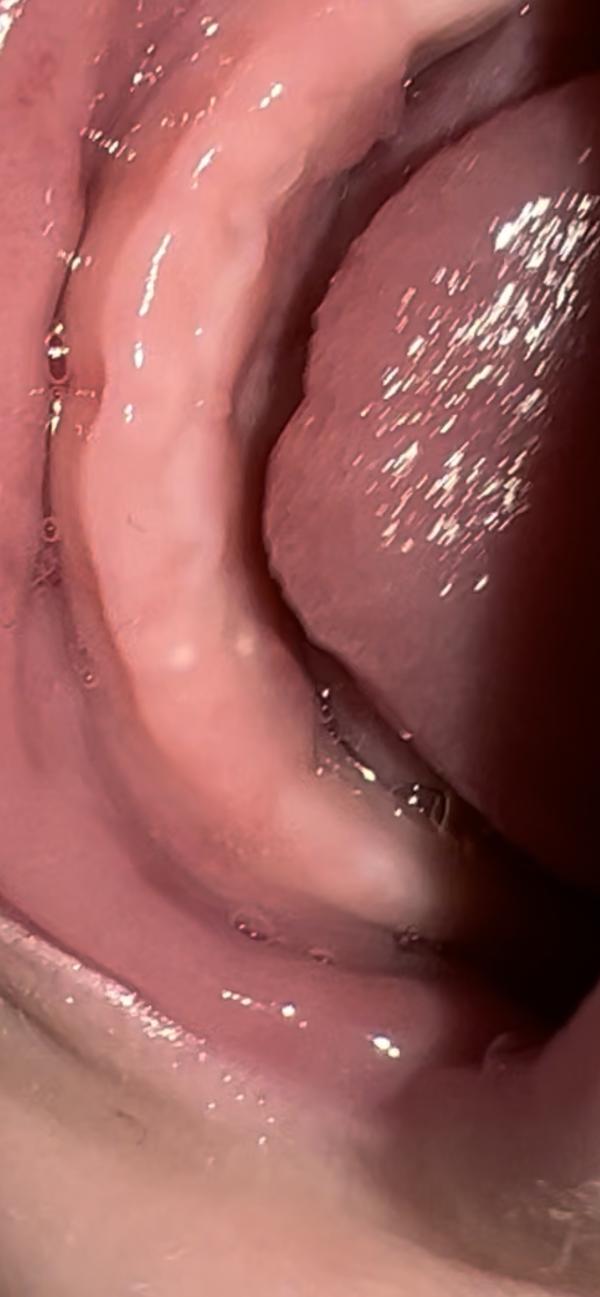

Дорогие мамочки , подскажите это зуб??

На зуб не похоже. Похоже на жемчужинку.. у нас уже есть зубки, поэтому знаю как выглядит)

У нас она такая капризная стала , все в рот тянет , слюни ручьём , до этого одна точка была , сейчас две . Возможность к врачу сходить появится только через неделю, во я и переживаю 😔

Жемчужница